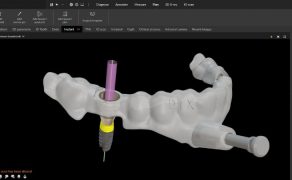

Most kompozytowy wzmocniony włóknem szklanym – nowoczesna alternatywa dla tradycyjnych uzupełnień

TITLE: Glass fibre reinforced composite bridge

– a modern alternative to traditional restorations

STRESZCZENIE: W artykule omówiono kliniczny

przypadek uzupełnienia braku zębowego poprzez wykonanie mostu

kompozytowego wzmocnionego włóknem szklanym.

SŁOWA KLUCZOWE:

wkład koronowy, włókno szklane, most kompozytowy

SUMMARY: This article discusses a clinical case of

the restoration of missing teeth with a glass fibre reinforced

composite bridge.

KEYWORDS: crown inlay, glass fibre, composite

bridge

Współczesna stomatologia realizuje wiele zadań, wśród których prym wiedzie odtwarzanie funkcji z jednoczesną poprawą estetyki uśmiechu. Brak pojedynczego zęba w łuku stanowi wskazanie do podjęcia leczenia jedną spośród kilku dostępnych metod. Konstrukcje metalowe licowane ceramiką czy uzupełnienia pełnoceramiczne nie mogą być wykonane w każdym przypadku klinicznym. Szczególnie u młodych pacjentów wykonanie tradycyjnych mostów uzupełniających utracone zęby, ze względu na konieczność szlifowania zębów, nie jest preferowaną metodą terapii. Problematyczne jest również wykonanie klasycznych mostów w przypadku istniejących rozległych wypełnień w obrębie zębów filarowych, leczonych w przeszłości endodontycznie ze względu na ich zmniejszoną wytrzymałość mechaniczną. Uzupełnienia oparte na implantach z różnych powodów również nie mogą być rutynowo zastosowane u każdego pacjenta.

Alternatywnym rozwiązaniem w takich sytuacjach może być adhezyjnie łączony z tkankami zęba most kompozytowy wzmocniony włóknem szklanym. Stosowane w stomatologii materiały kompozytowe składają się głównie z matrycy polimerowej ulegającej polimeryzacji oraz wypełniacza. W trakcie polimeryzacji kompo...